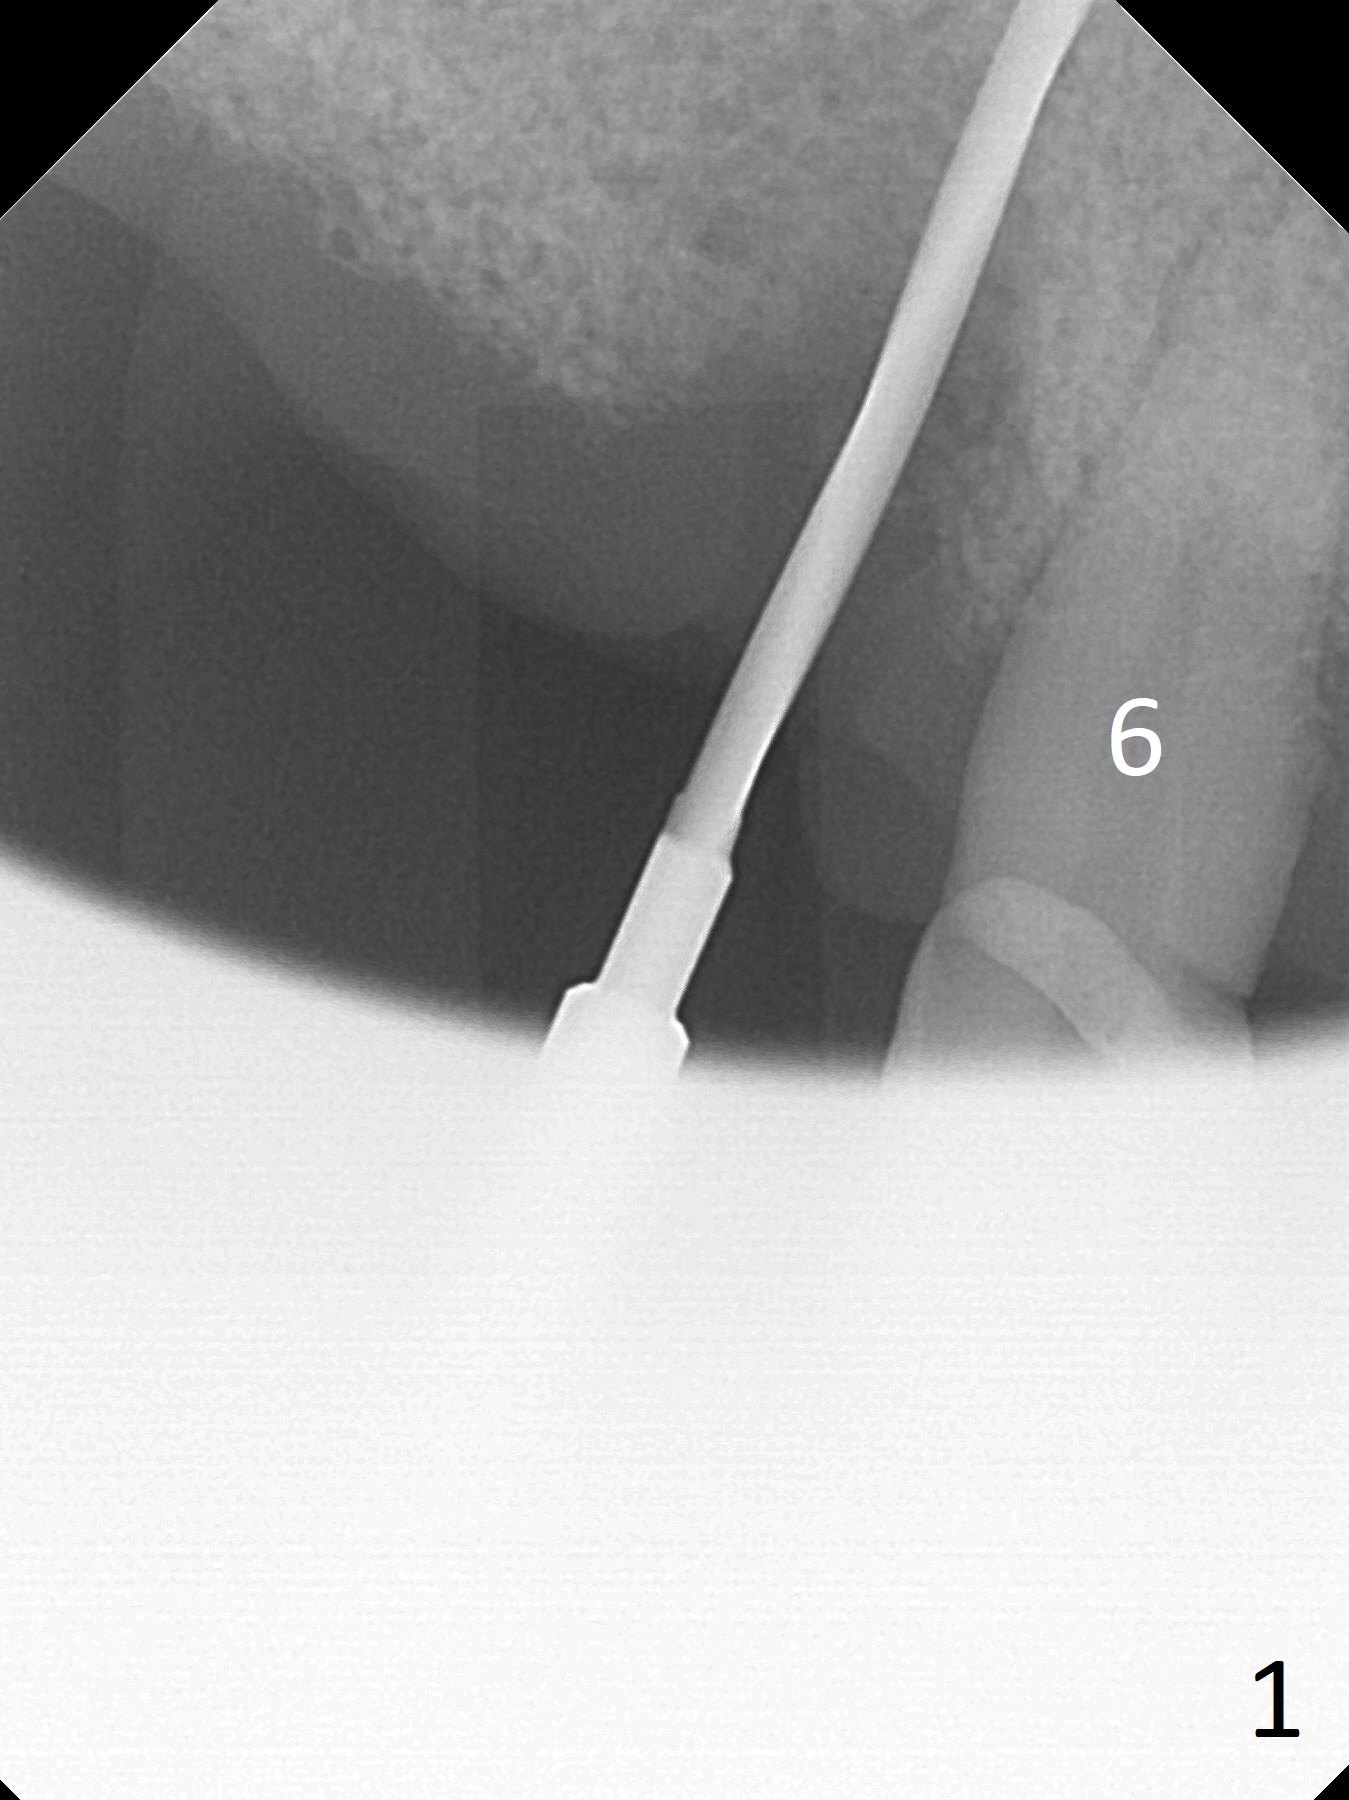

Extraction of the tooth #5 with mobility III reveals no buccal plate and low palatal plate. Osteotomy starts as palatal as possible (Fig.1). The bone density is low. After use of 2.7 mm drill (Fig.2), a 3 mm drill can be inserted into the osteotomy without resistance. A 4x16 mm implant is placed with insertion torque <30 Ncm. When an abutment is placed, the implant is found to have been placed distal. The implant is untorqued for change in trajectory. When a 4.5x7(5) mm abutment is placed, the abutment turns with the underlying implant (Fig.3). The former is kept to be turned with a hand driver until the latter is unable to turn. Following placement of allograft (Fi.g3,4 *), a mini-provisional is fabricated to retain the bone graft and at the same time not to be interfered with when a flipper is in and out. The bone graft in the former socket gap appears to have integrated into the native one 4.5 months postop (Fig.5).